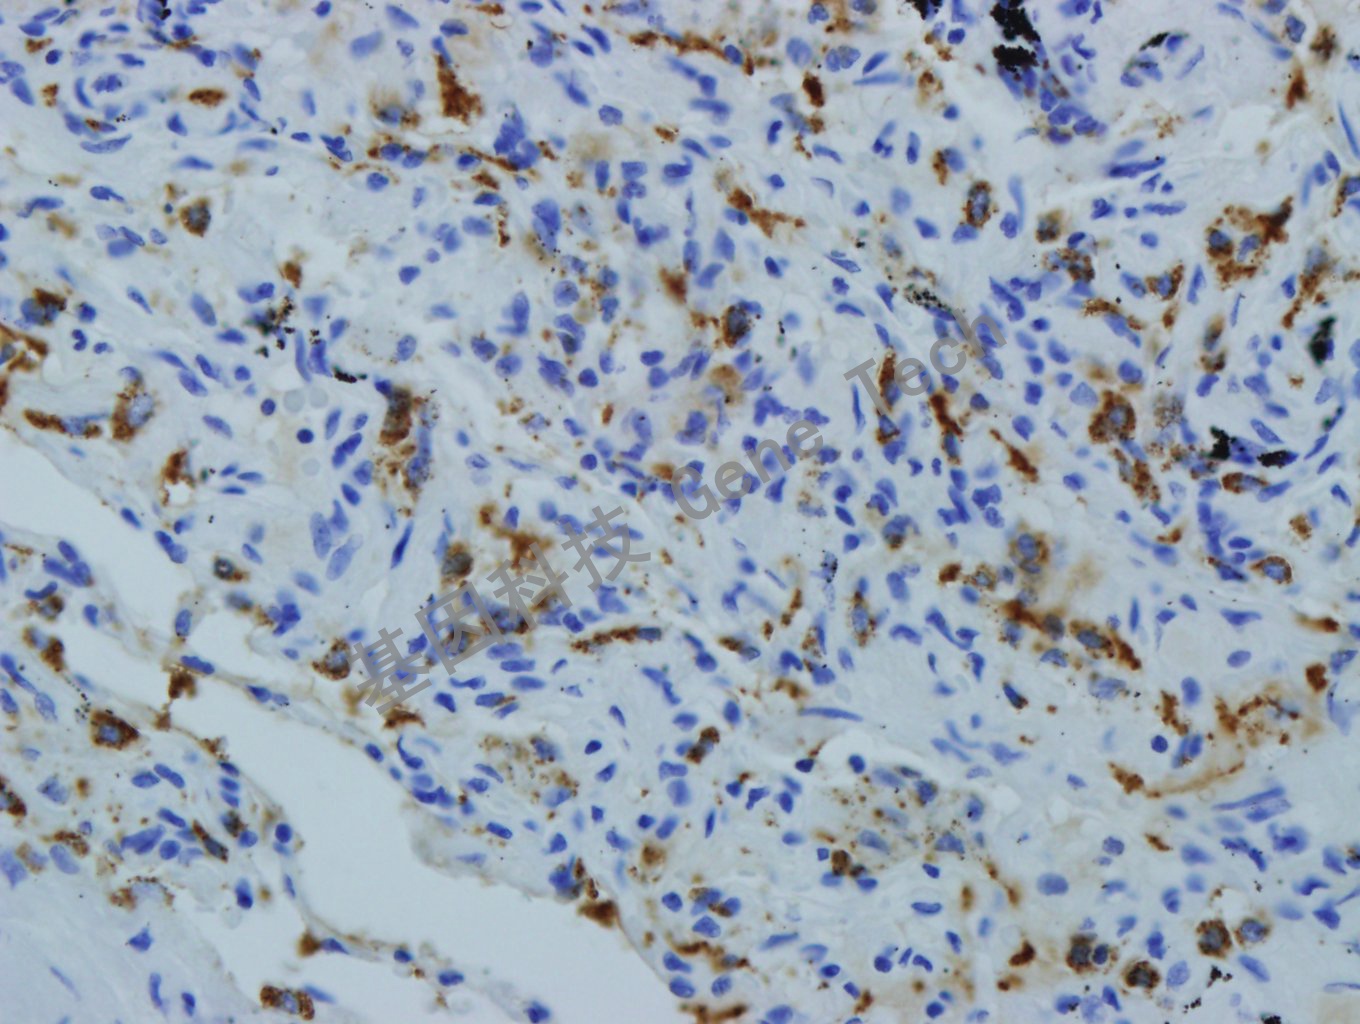

肺癌石蜡切片,用 SP-B(GT2277)染色,细胞浆阳性,DAB显色。(10×)

肺癌石蜡切片,用 SP-B(GT2277)染色,细胞浆阳性,DAB显色。(40×)